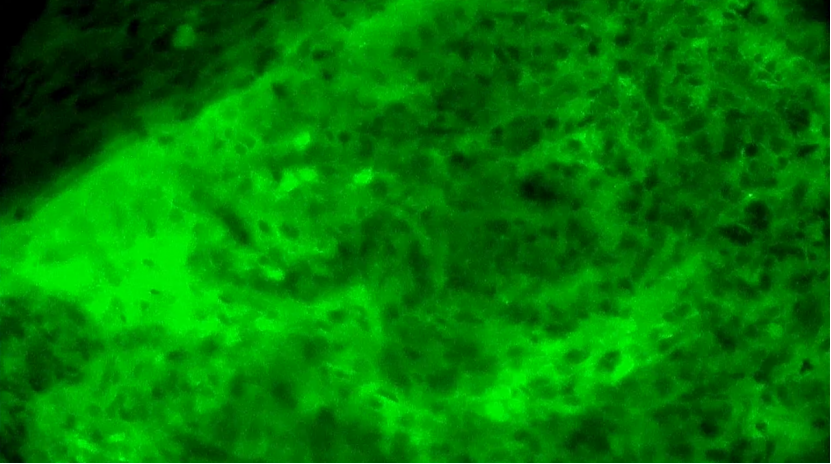

術(shù)中EndoSCell?細(xì)胞圖像如下:

第1次掃查離體腫瘤組織,細(xì)胞核異型性明顯,分布不規(guī)則且密度高,陽性。